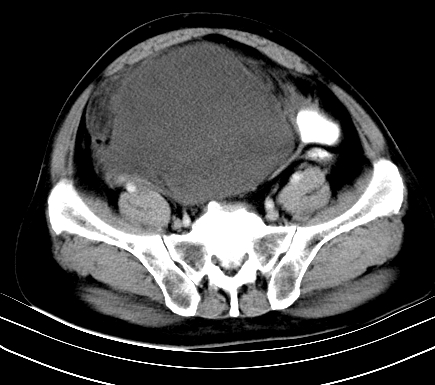

增强扫描

动脉期

【临床症状】

分析:

1、老年男性,易患恶性肿瘤;

2、腿痛就诊,一部分恶性肿瘤的患者会分泌一种激素,使凝血机能发生障碍,促下肢静脉血栓形成,致腿痛,有时往往为首发症状。因此,肿瘤不除外恶性肿瘤。

【ct表现】

1、肿块巨大,往往位于腹膜后,长大后才引起症状而就诊;那么位于腹膜后的肿瘤80%为恶性肿瘤。

2、实性肿瘤,增强扫描轻度不均强化,实性肿瘤一般不是好东西。

3、肿瘤边缘似见少许脂肪样密度。

4、腹膜后未见肿大淋巴结,但肿瘤于临近的肠管及组织接触紧密。

【诊断】

腹部占位,考虑位于腹膜后的恶性肿瘤,脂肪肉瘤(实体型)可能性大。

【分析】

1、腹膜后的肿瘤少见,但种类繁多,包括脂肪肉瘤、纤维组织细胞肉瘤、纤维肉瘤、平滑肌肉瘤、恶性畸胎瘤、神经肉瘤、神经母细胞瘤、血管肉瘤及横纹肌肉瘤等,其中脂肪肉瘤为较常见的一种肿瘤。

2、增强扫描强化不明显,除脂肪肉瘤以外,一般肿瘤强化中度以上。脂肪肉瘤可不强化或轻度强化。

术后病理结果:腹膜后脂肪肉瘤。